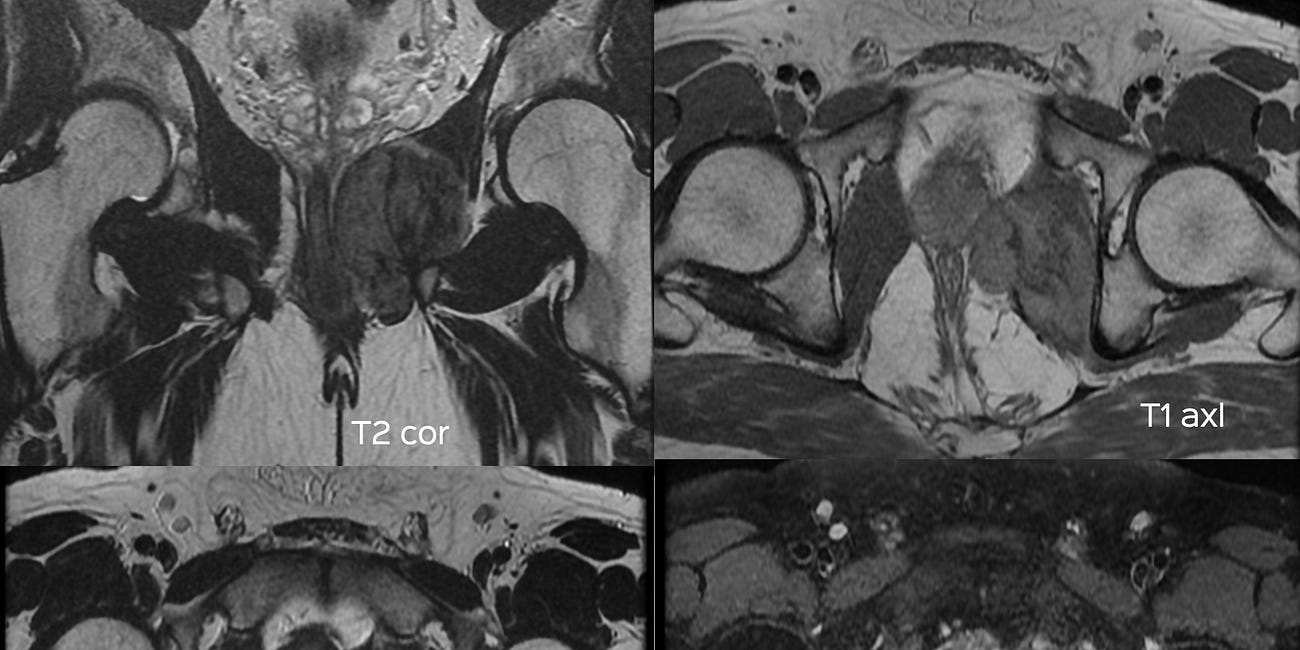

This 51-years old presented with erratic coccygeal pain. The MRI showed these findings.

The patient’s symptoms and MRI did not match. A PET/CT was then done for further work-up.